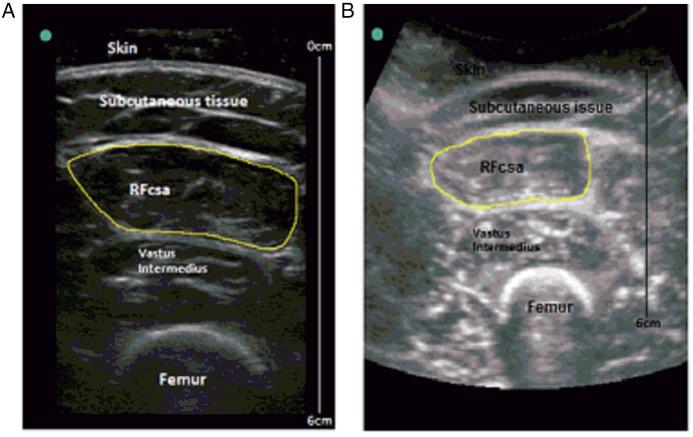

Ultrasound measurements of rectus femoris cross-sectional area (RFCSA) are clinically useful measurements in chronic obstructive pulmonary disease (COPD) and critically ill patients. Technical considerations as to the type of probe used, which affects image resolution, have limited widespread clinical application. We hypothesised that measurement of RFCSA would be similar with linear and curvilinear probes.

Study 1 showed demonstrated no difference in the measurement of RFCSA using the curvilinear and linear probes (308±104 mm(2) vs 320±117 mm(2), p=0.80; intraclass correlation coefficient (ICC)>0.97). Study 2 demonstrated high intra-rater and inter-rater reliability of RFCSA measurement with ICC>0.95 for both. Study 3 showed that the spliced image from the linear probe was similar to the whole image RFCSA (308±103.5 vs 263±147 mm(2), p=0.34; ICC>0.98). Study 4 confirmed the clinical acceptability of using the curvilinear probe during an exacerbation of COPD. There were relationships observed between admission RFCSA and body mass index (r=+0.65, p=0.018), and between RFCSA at admission and physical activity levels at 4 weeks post-hospital discharge (r=+0.75, p=0.006).

These studies have demonstrated that clinicians can employ whole and spliced images from the linear probe or use images from the curvilinear probe, to measure RFCSA. This will extend the clinical applicability of ultrasound in the measurement of muscle mass in all patient groups.